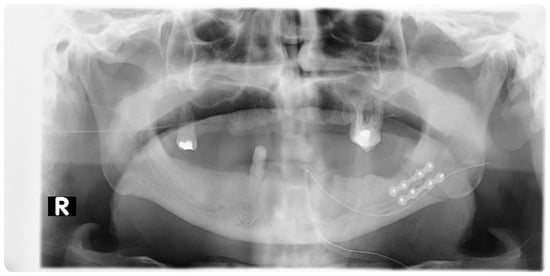

2. Materials and Methods